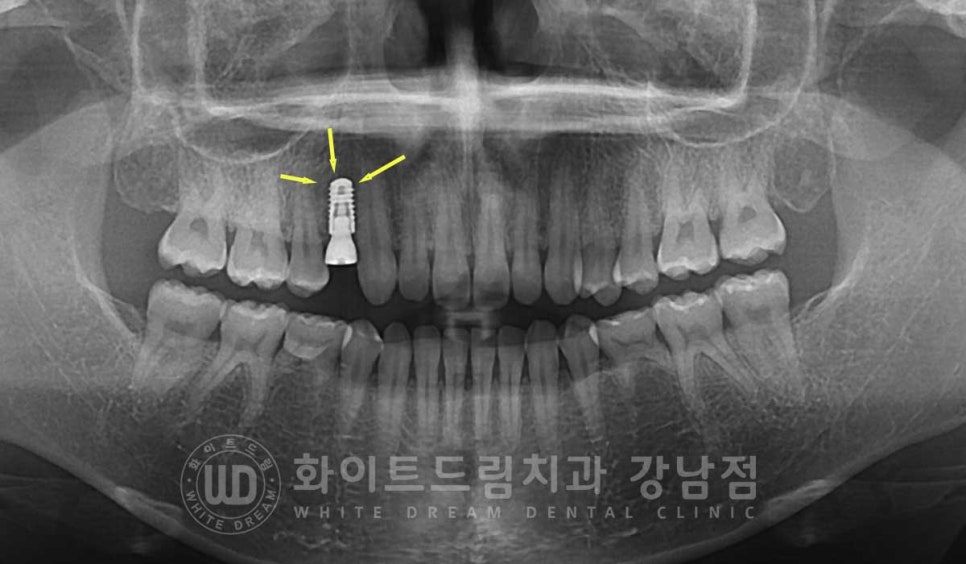

잇몸뼈가 풍성하고 건강한 상태이기에 추가적인 뼈이식 없이

발치 후 즉시 임플란트 식립을 진행했습니다.

이렇게 인접치 사이에 임플란트를 식립할 때는

주위 인접치와 평행선을 이루도록 식립 방향(path)를 잘 잡고 진행해야 합니다.

환자분은 23.08.04 식립 후 4개월 뒤 임플란트 보철 세팅을 진행했고

총 5개월의 치료 기간으로 모든 치료가 마무리되었답니다.

치료 기간 23.08.04 - 24.01.05